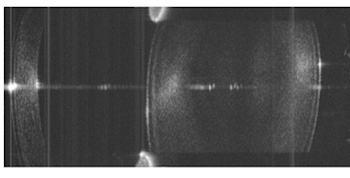

OCT image of the eye's anterior segment

Quasi-simultaneous imaging of the whole eye was achieved using the retinal imaging configuration, but moving the ETL and offset lens further back to provide greater beam divergence. From that position, the resulting beam at the pupil plane could be either collimated (via low ETL current) or focused (high ETL current), with images of the anterior segment and retina acquired alternately.